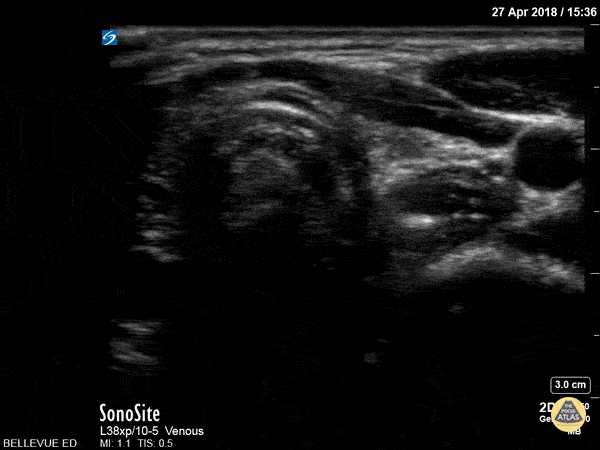

Soft Tissue - Thyroid Left Lobe

In this view we see half of the thyroid gland, which has similar echogenicity to the liver. The thyroid isthmus overlies the trachea, while the left thyroid lobe overlies the esophagus and is medial to the left carotid artery. Hannah Kopinksi and Dr. Lindsay Davis - NYU Emergency Medicine